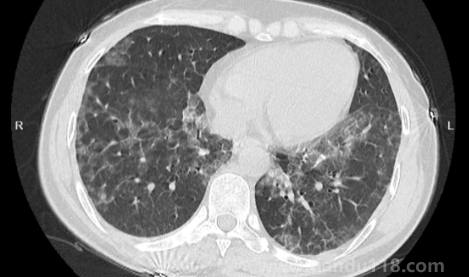

新冠白肺可逆嗎(新冠肺部白化能恢復(fù)嗎) 新冠白肺可逆嗎(新冠肺部白化能恢復(fù)嗎)新冠白肺是比價(jià)常見的一個(gè)癥狀,現(xiàn)在無(wú)論老人還是年輕人如果新冠感染一直咳又不康復(fù)的話,可能會(huì)出現(xiàn)白肺或者肺炎的情況。那么,新冠白肺可逆嗎?84歲老人肺全白有救嗎?一... 小編 2023-01-09 889 #新冠 #白肺

如何自查是否出現(xiàn)白肺(肺白了還能恢復(fù)嗎) 如何自查是否出現(xiàn)白肺(肺白了還能恢復(fù)嗎)白肺是目前很常見的情況,受新冠影響很多老年人都出現(xiàn)了白肺的情況,當(dāng)然也有年輕人會(huì)患上白肺。那么,如何自查是否出現(xiàn)白肺?平時(shí)怎樣保護(hù)自己的肺?一起來(lái)看看天都生活網(wǎng)... 小編 2023-01-06 874 #白肺